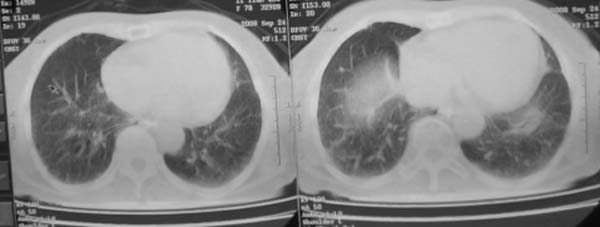

女,78岁,声嘶月余,否认有既往病史,有粉尘接触史10年。

颈部见多枚淋巴结肿大,考虑尘肺继发结核,喉部淋巴结钙化,不除外喉部慢性淋巴结炎、喉淀粉样变及类癌等

肺癌伴纵膈、双颈部淋巴结转移;尘肺。

双上肺结节融合影,周围有纤维条索影,结合粉尘接触史,首先考虑尘肺。双侧颈部有增大淋巴结,有声嘶表现,肺癌淋巴结转移不能排除。可结合颈部淋巴结活检。